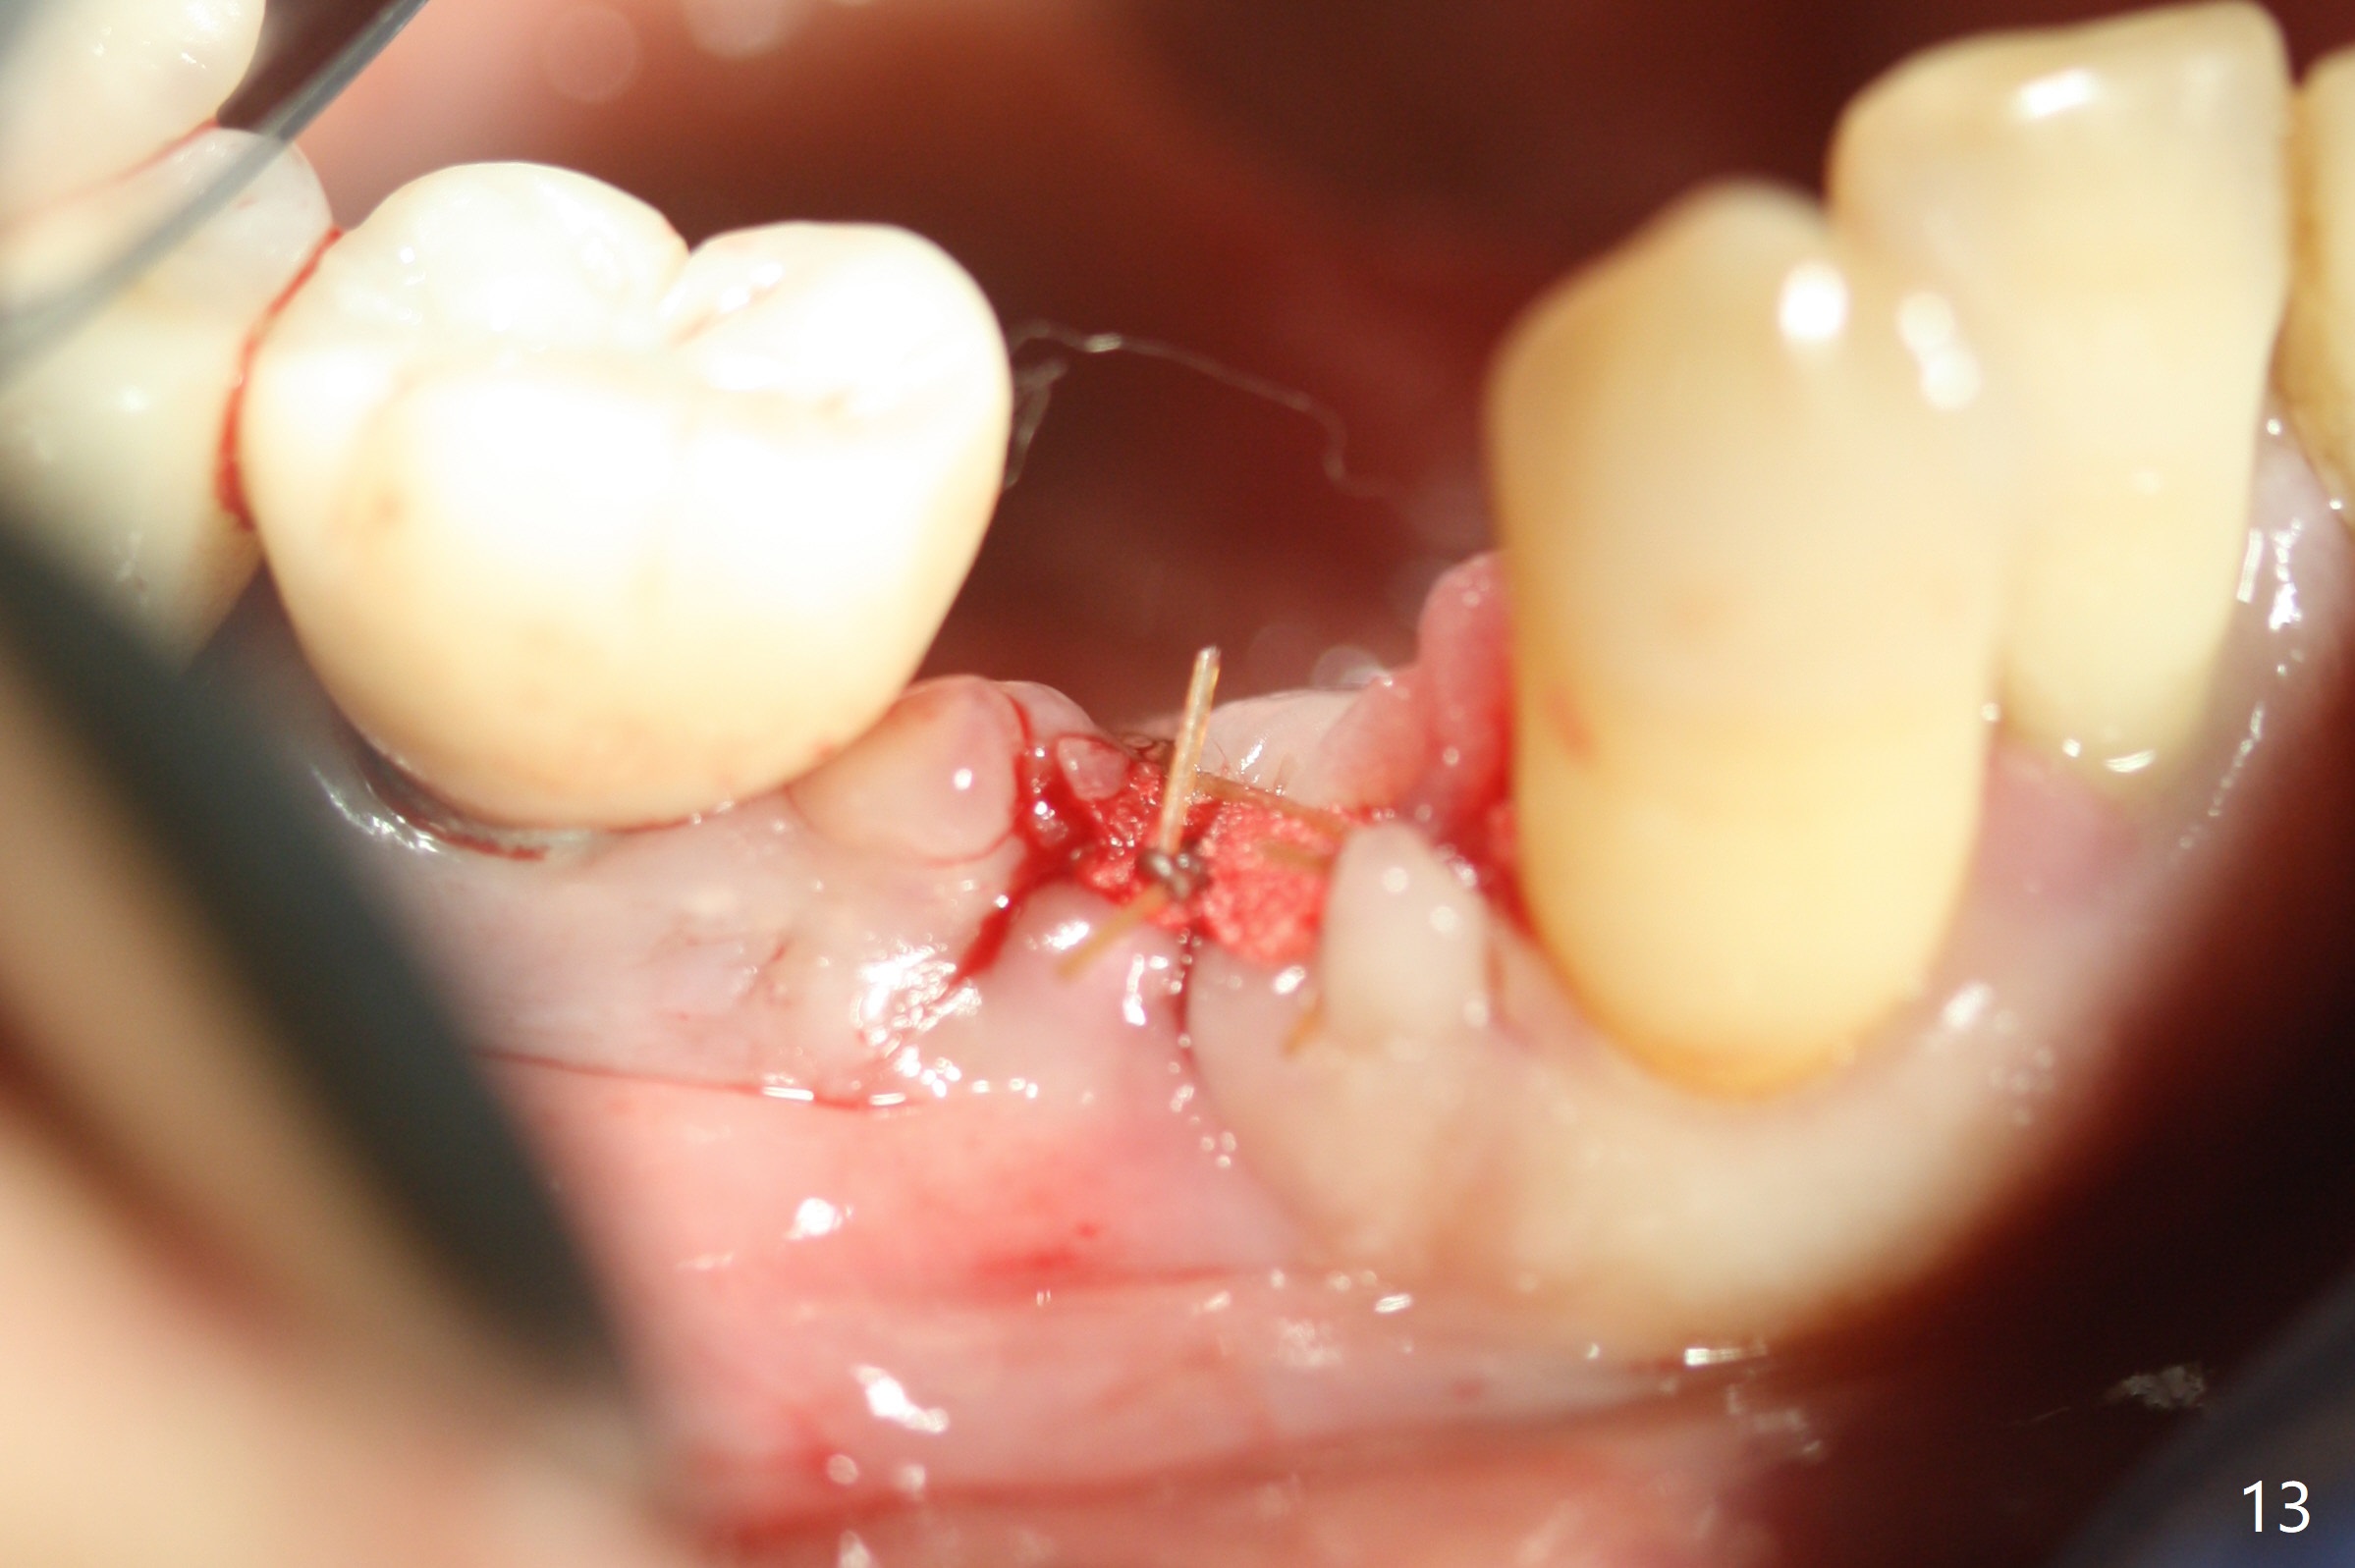

The affected tooth (#28) has buccal gingival recession (Fig.1). As expected, the buccal plate is found low after extraction. Osteotomy is established in the lingual slope of the socket with 1.5 mm drill for 13 mm (Fig.2,3). Following use of Magic Drill 3.3 mm for 13 mm, a 4x11 mm dummy implant is incompletely seated (Fig.4); it is also close to the Mental Loop (Fig.4 red line). After use of Final Drill, a 4x9 mm IBS implant is placed 4 mm and 2 mm subgingival buccal and lingual, respectively (Fig.5) with a large buccal gap (Fig.6 (40 Ncm)). After placement of allograft in the peri-implant space (Fig.7 *), a 4.5x5.7(4) mm abutment is placed (A). A piece of gauze is placed in the remaining buccal space prior to provisional fabrication (Fig.8 *). The space occupied by the gauze is later filled with collagen plug before provisional seating. The gingiva is healthy around the provisional 12 days postop (Fig.9). To reduce buccal gingival recession, the buccal margin of the provisional is shortened 4.5 months postop (Fig.10 arrow). PA taken 5.5 months postop is shown with the implant at 31. The lingual gingiva is erythematous, edematous, and recessive with +BOP and deep pockets 14 months postop (Fig.11). It appears that the small and short implant is not favorable for healing. The infected implant is removed with the missing buccal plate; bone graft is placed 15 months postop (7 months post cementation, Fig.12,13).